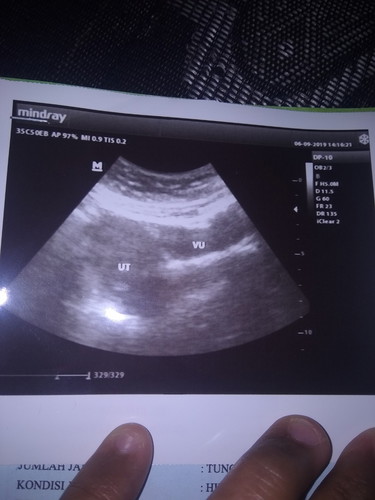

Aku tadi USG Bun tapi diusg aku gak hamil Bun aku udah tespak Bun sebelum USG perkiraan hpht aku usia 10week 3day Bun dan tadi sesudah diusg sama dokter ny suruh tespack lagi dan hasil ny positif yang salah dimana ya Bun dan saya langsung drop banget nih Bun mohon solusi ny dong bun terima kasih belum ny